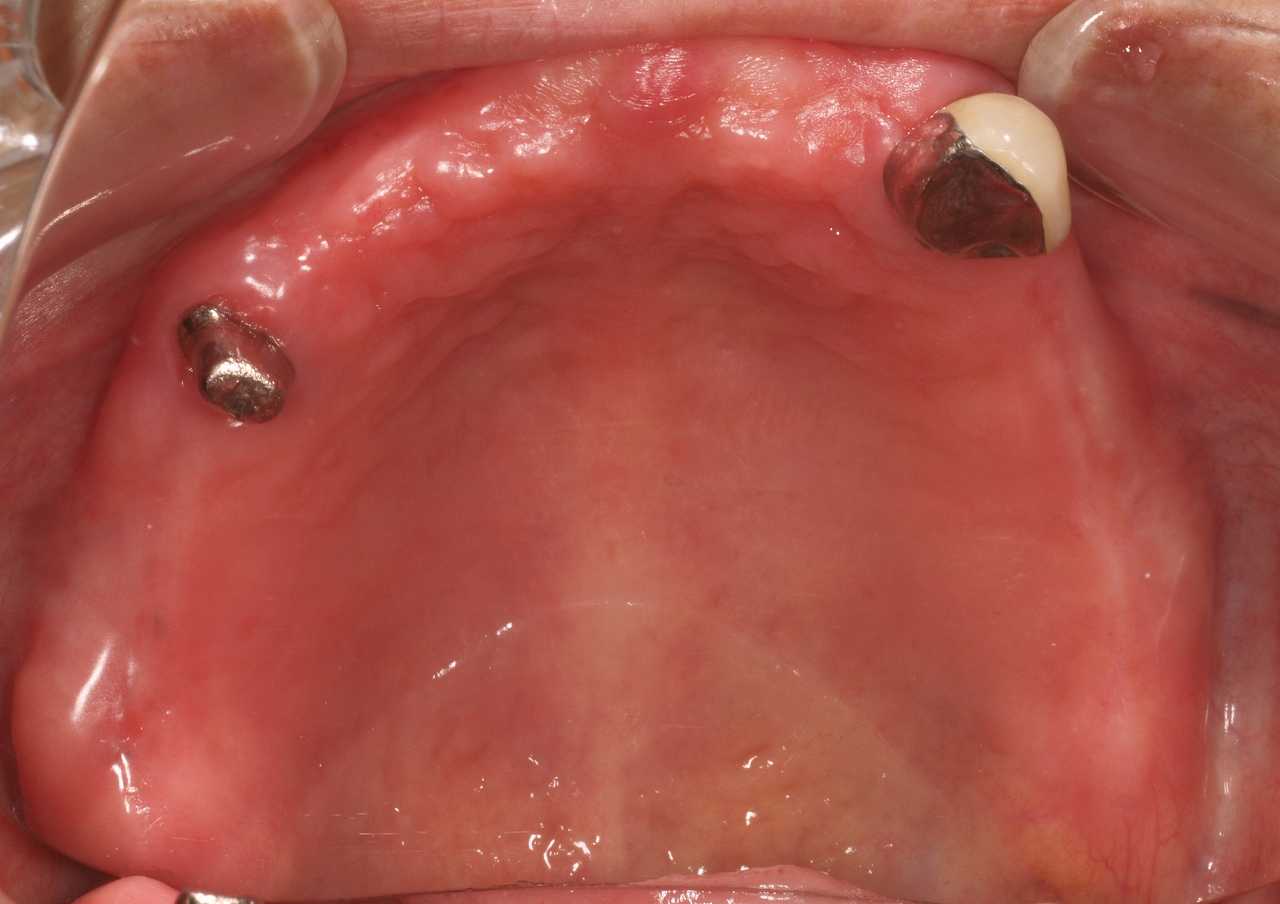

自由診療の入れ歯 上顎は金属床 下顎は柔らかいシリコンを貼り付けた快適な入れ歯|お知らせ |広島市安佐南区の歯科医院 自由診療の入れ歯 上顎は金属床 下顎は柔らかいシリコンを貼り付けた快適な入れ歯 トップ お知らせ・ブログ お知らせ 自由診療の入れ歯 上顎は金属床 下顎は柔らかいシリコンを貼り付けた快適な入れ歯 自由診療の入れ歯 上顎は金属床 下顎は柔らかいシリコンを貼り付けた快適な入れ歯 上顎正面観 2本だけ歯が残っています 右上は弱くなっているためコーヌスにて作成 問題は下顎です 顎堤の高さがなく入れ歯の安定が悪そうです 上顎の金属床 顎堤が吸収した時のためにも公演はレジンにしています 下顎の入れ歯 顎舌骨筋のアンダーカットまでシリコンが維持のために行くようになっています このような外形です Web診療予約 初めての方へ 選ばれ続ける理由 院内設備について 歯が痛いしみる一般歯科 歯がぐらぐらする歯周病 健康な歯を保ちたい予防歯科 子供の虫歯予防をしたい小児歯科 銀歯をセラミックに審美歯科 白い歯を目指しませんか?ホワイトニング 矯正専門医がいるので安心矯正歯科 抜けた歯を補いたいインプラント・入れ歯 医院案内 スタッフ紹介 メリィハウス歯科クリニックオフィシャルホームページ ラベンダー歯科クリニックオフィシャルホームページ お知らせ・ブログ ホーム 診療科目 一般歯科 歯周病治療 予防治療 小児歯科 審美治療 ホワイトニング 矯正歯科 入れ歯・インプラント マウスピース矯正 初めての方へ 院長・スタッフ 設備紹介 医院案内・アクセス メニューを閉じる